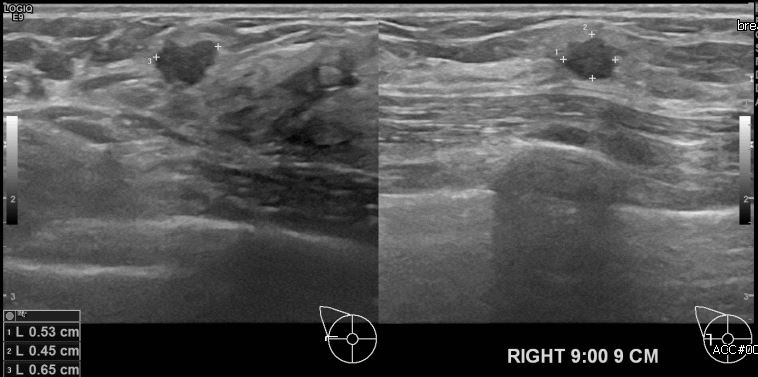

우측 유방의 멍울로 내원하신 40대 여성분으로 본원 초음파상 우측 9시 방향에

9cm 떨어진 거리에 의심스러운 멍울 조직검사 시행하여 우측 침윤성 유관암 진단 되었습니다.